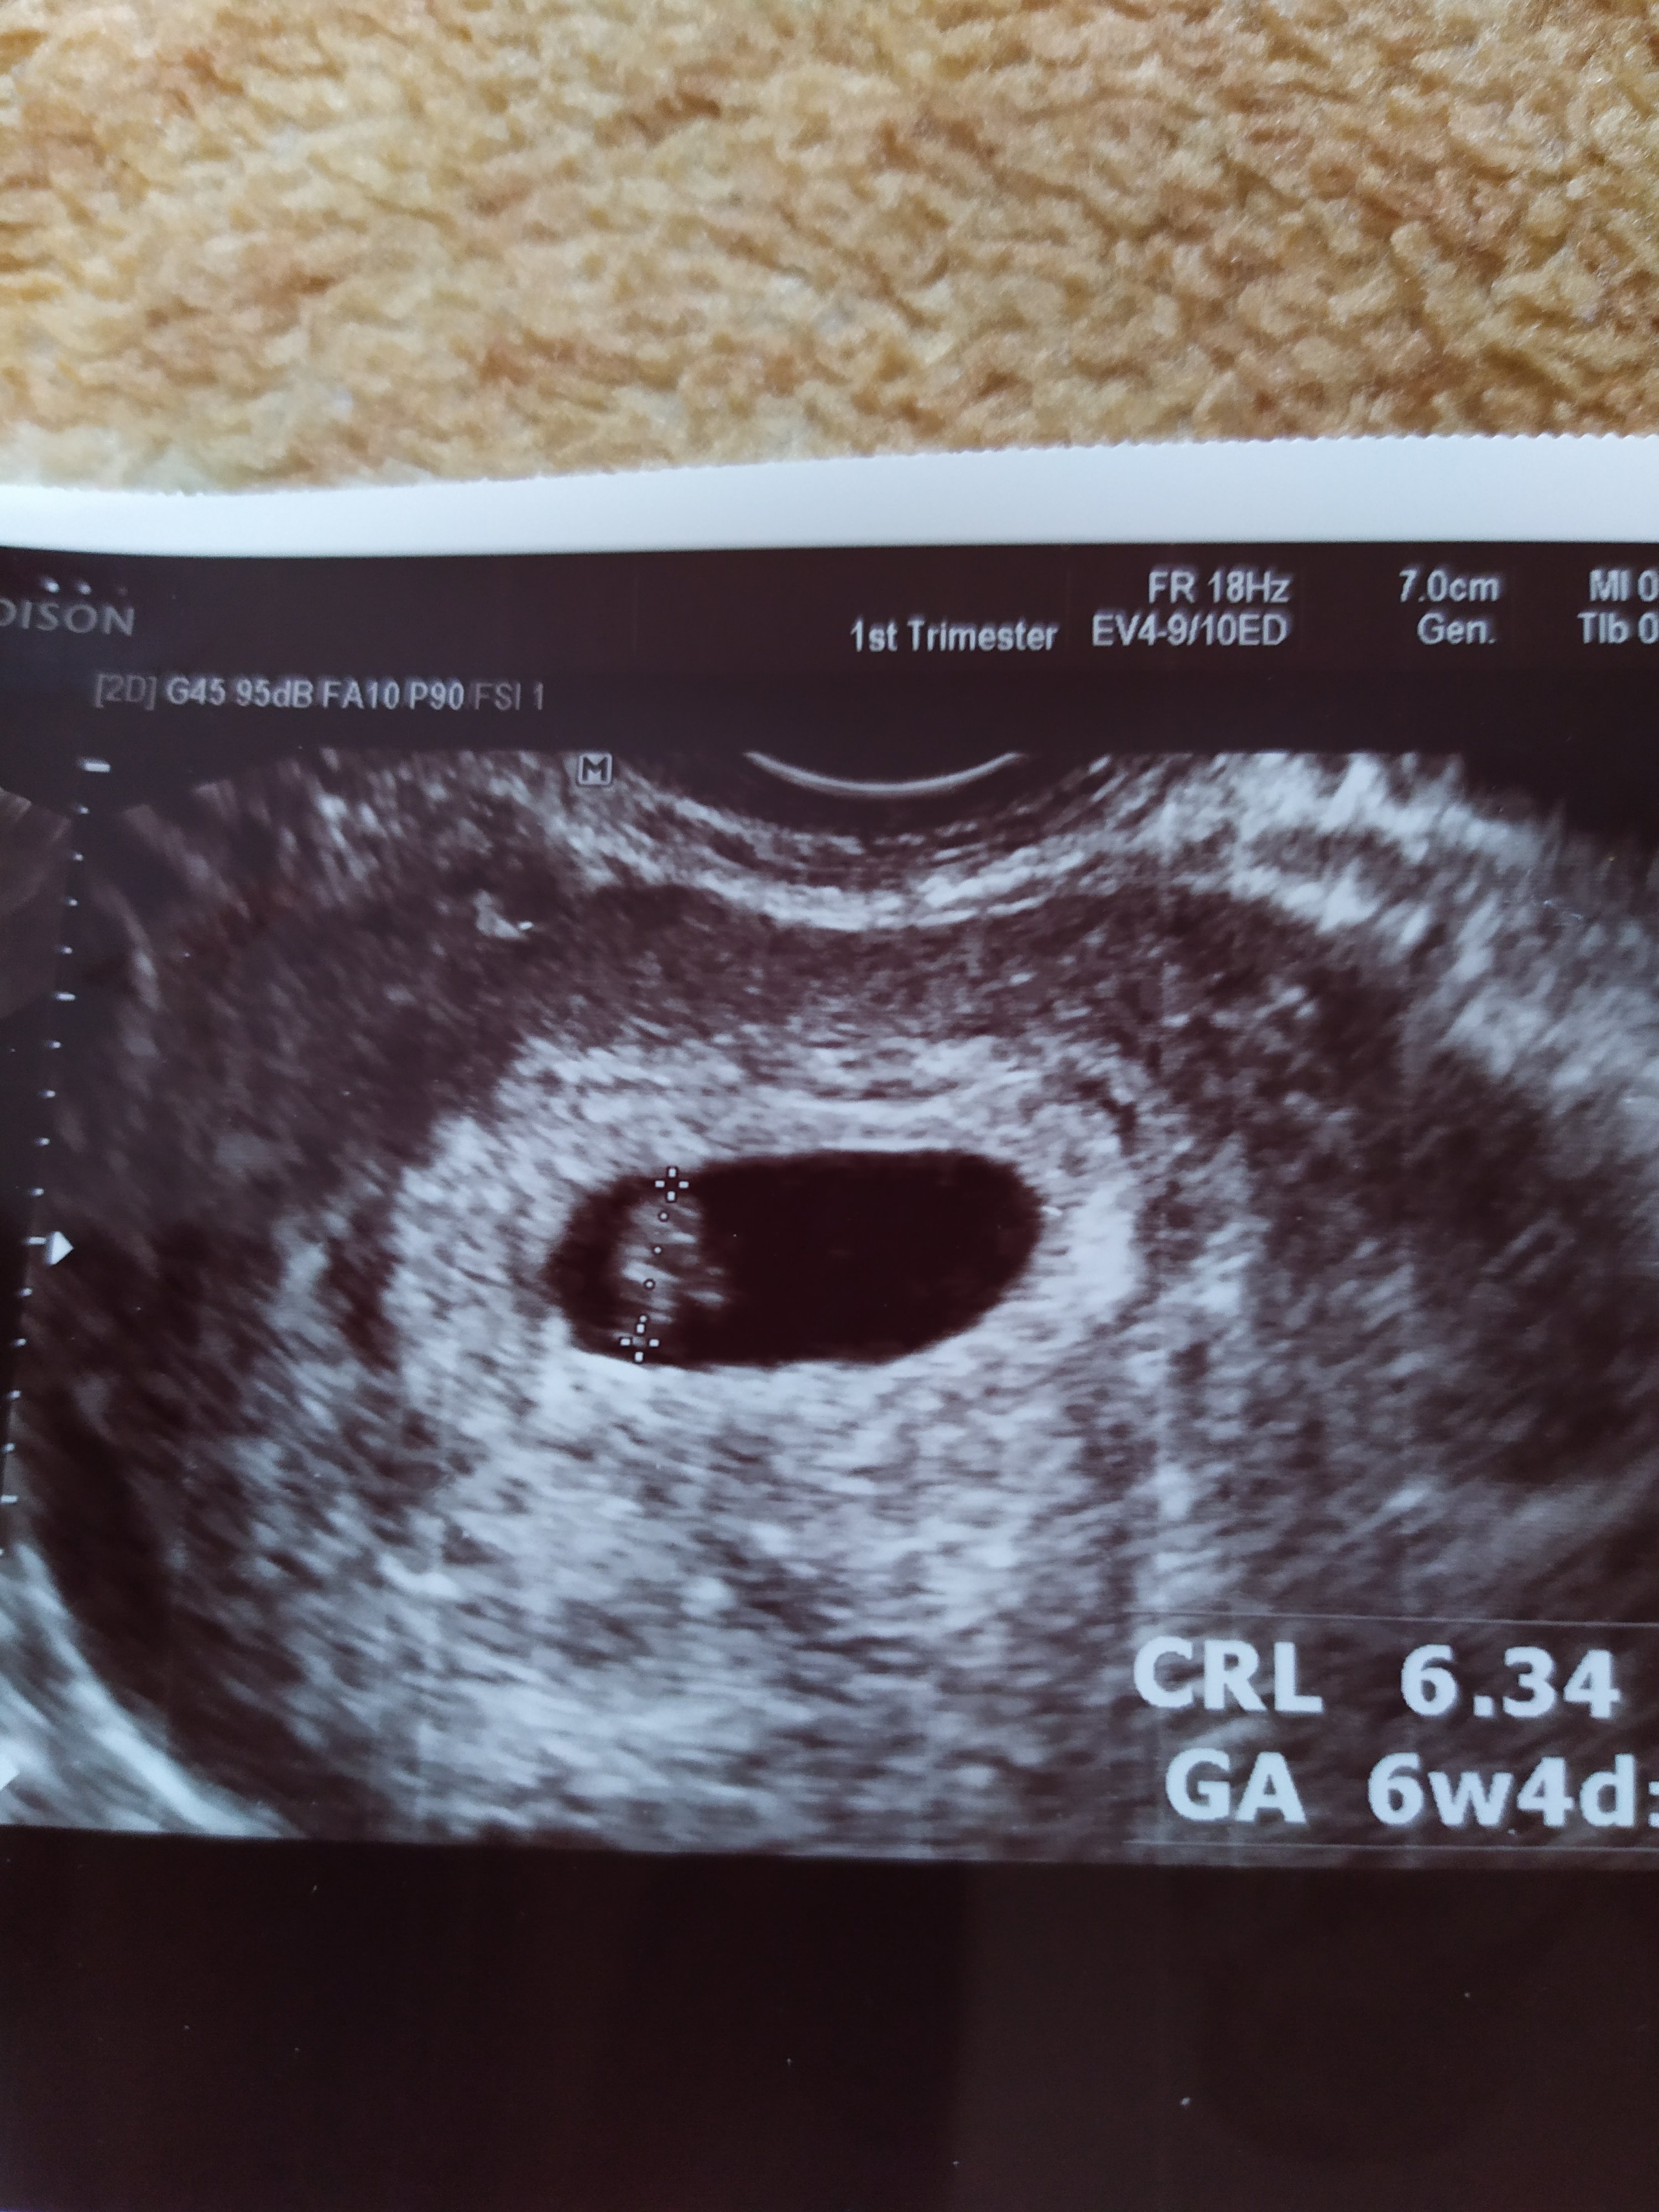

Zazdroszczę tym z Was, które potrafią się cieszyć tym co nas czeka w najbliższym czasie. Ja jestem cała w stresie o to czy wszystko pójdzie dobrze. Według kalkulatorów jestem teraz w 6tc+3dni i strasznie mi odbija. Pierwszy raz u gin byłam w 5tyg+2dni i GS było dopiero 3,6 mm, jak przeczytałam że niektóre z Was miały już w tym czasie 8-12 to w ogóle zwariowałam.

Najbardziej nie wiem co myśleć bo lekarz mówi że wszystko wygląda dobrze, potwierdził to też przedwczoraj jak poszłam na szybką konsultację, a znowu jak czytam artykuły, albo tu na forum to ta moja ciąża jakaś opóźniona.